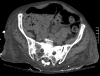

Fecal impaction (FI) is a common cause of lower gastrointestinal tract obstruction lagging behind stricture for diverticulitis and colon cancer. It is the result of chronic or severe constipation and most commonly found in the elderly population. Early recognition and diagnosis is accomplished by way of an adequate history and physical examination in conjunction with an acute abdominal series. Prompt identification and treatment minimizes the risks of complications such as bowel obstruction leading to aspiration, stercoral ulcers, perforation, and peritonitis. Treatment options include gentle proximal softening in the absence of complete bowel obstruction, distal washout, and manual extraction. Surgical resection of the involved colon or rectum is reserved for cases of FI complicated by ulceration and perforation leading to peritonitis. Recurrence is common, and can be managed by increasing dietary fiber content to 30 gm/day, increased water intake, and discontinuation of medications that can contribute to colonic hypomotility.